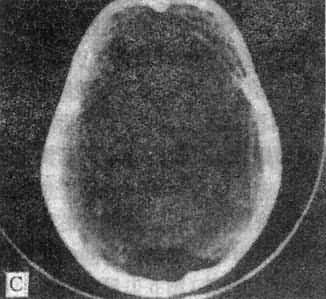

10mm底颅层面 此层面通过眦耳线上方10mm,由前向后可见眼眶上部、蝶窦和中颅凹底、枕骨及枕大孔等颅底结核。20mm蝶鞍层面 可见垂体、四脑室桥池和桥小脑角池、岩锥与内耳道、前、中和后颅凹脑组织结构。本层面重点观察垂体和后颅凹结构。(图5-1-4A)。30mm鞍上池层面 可见鞍上池呈六角星或五角星形低密度脑脊液间隙,增强CT扫描尚可见脑底动脉环在池内的分布情形(图5-1-4B)。鞍上池后方、环池四叠体池包绕部分即为中脑。40mm三脑室前部层面 重点观察内囊、基底节和丘脑区(图5-1-4C)。50mm三脑室后部层面除显示内囊、基底节和丘脑区外,同时是观察三脑室后部松果体区重点扫描层面(图5-1-4D)。60mm侧脑室体层面可观察侧脑室体部、三角区和后角(图5-1-4E);增强CT尚可见直窦上矢状窦大脑镰强化显影。70mm侧脑室顶层面 可见侧脑室顶部、大脑纵裂、脑皮质脑髓质(图5-1-4F)。80~100mm脑室上层面 脑皮、髓质、脑沟和大脑纵裂清楚显示。

图5-1-4 正常头部CT扫描

A、蝶鞍一鞍上池层面,鞍上池和后颅凹同时显示,

B、鞍上池层面增强扫描,可见颅底动脉环显形

C、第三脑室前部层面 D、第三脑室后部层面

E、侧脑室体部层面 F、侧脑室顶层面